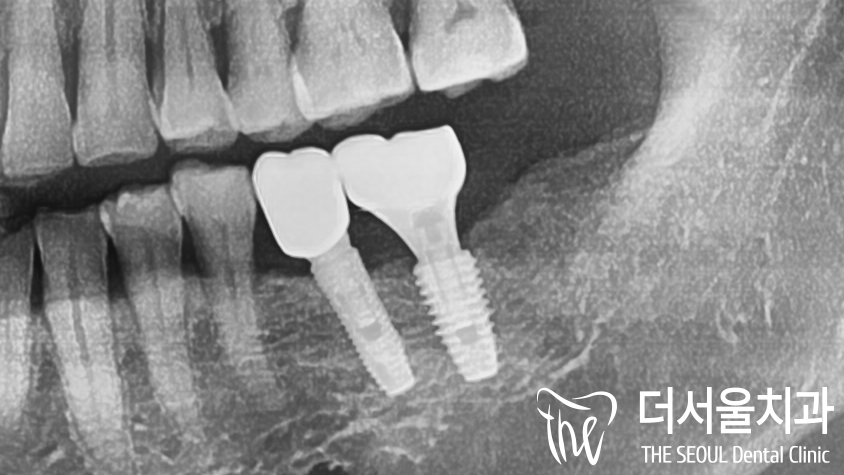

몇달이 지나고,

단단하게 심어져 있는 것을 확인한 뒤에

최종보철을 올려드린 모습입니다.

보기 좋게 만들어지지 않았나요?

옆에 있던 기존 보철과도

위화감 없이 잘 어우러지고 있습니다.

어금니 임플란트 ,

정말 성공적으로 마무리 되었네요^^